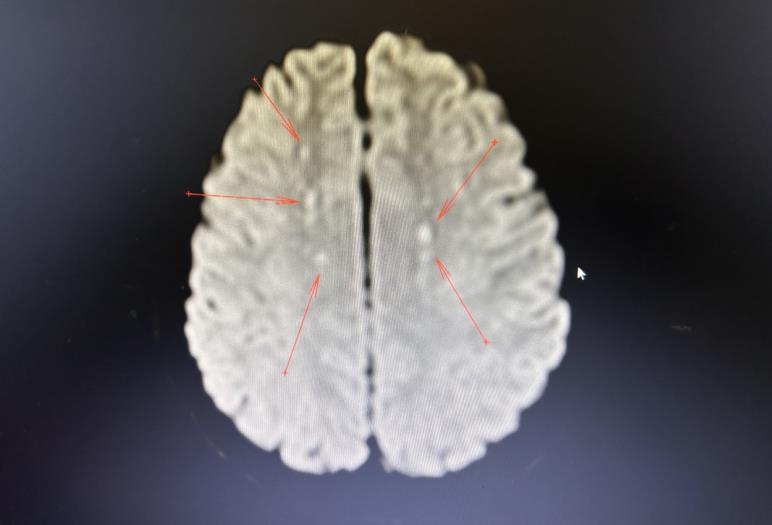

该患者住院第二天突然出现意识下降(GCS10分),失语,躁动不安,呼唤稍有轻微反应,伴随呼吸急促,心率快,口唇轻度紫绀,指脉氧下降,查肺动脉CTA提示肺栓塞,情况紧急,医院重症医学科(ICU)医生立刻参与会诊,并立即将病人转入ICU进行救治。ICU立即加强氧疗,抗凝溶栓处理,病人指脉氧迅速改善,面色红润,但病人意识障碍加重(GCS9分)。ICU钟瑜主任医师详细查看病人,充分了解病史,结合症状、体征及检查检验结果后得出诊断:病人此种情况属于脂肪栓塞综合征,指示予溶栓、抗凝、激素等处理,并完善颅脑MRI检查,证实为急性脑梗死。

患者经ICU积极治疗后,在住院第4天完全清醒,言语流利,对答切题,肢体活动良好。由于病情危重,暂时无法行手术治疗,入院后行骨牵引固定,减轻骨折处疼痛。于住院第6天顺利转出普通病房。住院第11天,复查颅脑CT提示梗死病灶完全消失。病情稳定后于住院第17天行手术治疗,住院第31天顺利出院。

2. 神经表现:80%FES患者会出现神经症状,通常出现在肺部症状之后。表现为嗜睡、神志不清、烦躁不安、谵妄、癫痫和昏迷,并可发展为局灶性缺损,如偏瘫和失语症以及癫痫和昏迷。多数神经系统症状在有效治疗后可以消失。长骨骨折后伴发癫痫或无相关骨科创伤出现的癫痫也可能是发生了FES,无骨折发生癫痫的FES发病机制被认为是继发于软组织损伤。难治性癫痫持续状态和非惊厥性癫痫持续状态可能是FES的主要神经学表现。